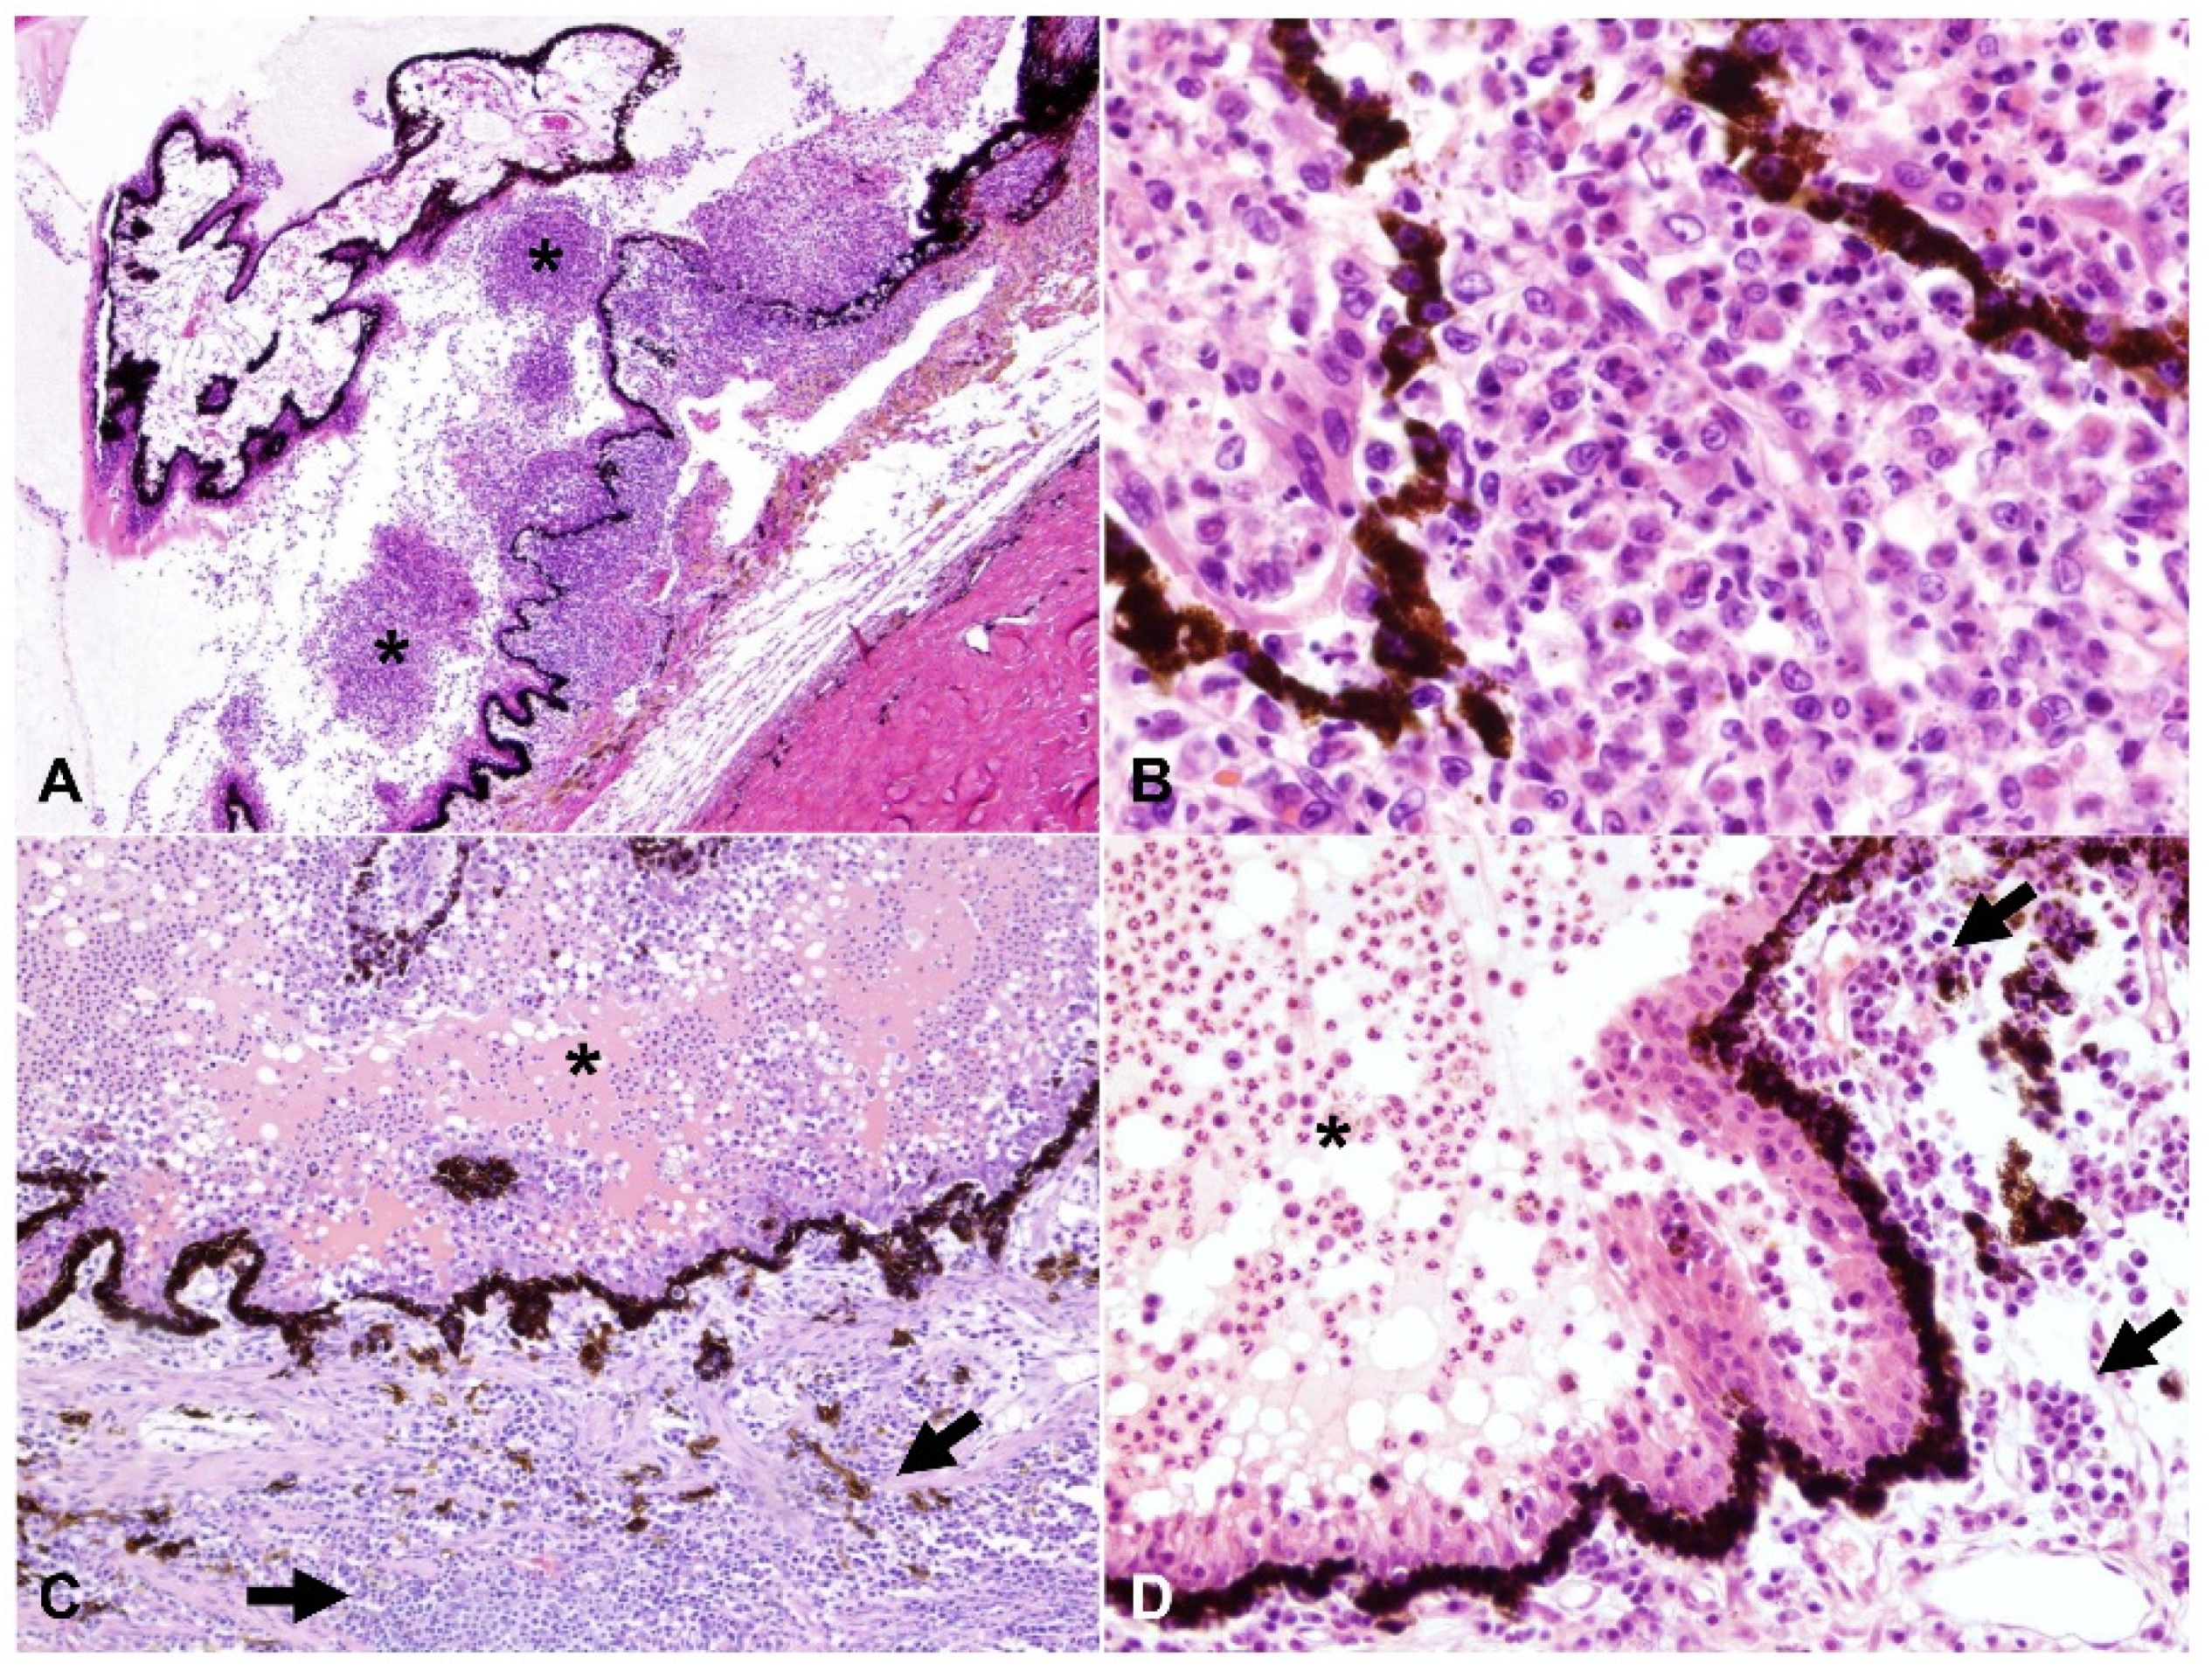

Figure 2.

Cyclitis with variable pyogranulomatous and plasmacytic inflammation, H and E: (A–D) the posterior chamber is filled with intense pyogranulomatous exudate (asterisks), while the stroma of the pars plicata of the ciliary body is markedly expanded by either similar pyogranulomatous (A,B) or by plasmacytic infiltrate (arrows, (C) and (D)); (A) 40× total magnification; (B) 200× total magnification; (C) 100× total magnification; (D) 200× total magnification.

Frequency of pyogranulomatous vs. plasma cell-rich inflammation in the uvea is shown in Figure 1. Inflammation within the anterior uvea was predominantly plasmacytic in all 24 cases with iritis and in 88.5% (23/26) of cases with cyclitis. The infiltrating inflammatory cells in the iris mostly expanded the posterior aspect of the iris with less infiltration of the anterior stroma. The plasmacytic infiltrate within the ciliary body was often more heavily concentrated in the pars plicata (Figure 2), and although there was commonly peri-uveal exudate overlying the ciliary body (14/30 cases overall, and 14/26 cases with cyclitis), the plasma cells remained within the uveal stroma or epithelium in each case. The exudate overlying the pars plicata of the ciliary body and posterior iris epithelium was pyogranulomatous in all 14 cases in which it was noted (Figure 2). In most cases, this peri-uveal exudate was concentrated in the anterior peripheral vitreous and present to a lesser extent in the posterior chamber. The inflammatory infiltrate within the uveal tract displayed a superior–inferior polarity in 17 cases, with more severe inflammatory infiltrate in the superior (tapetal) uveal tract in 12 of these 17 cases. In the eight cases in which both eyes were available for examination, the degree of inflammation was similar between the two.

Amongst all 30 cases, we found the following unique characteristics in cases of ophthalmitis attributed to FIP: (1) cases with moderate to marked cyclitis often had interstitial and intraepithelial plasmacytic infiltrate, with pyogranulomatous peri-uveal exudate overlying the pars plicata (Figure 2); (2) there was more severe inflammatory infiltrate in the superior uveal tract in 12/17 cases that displayed superior–inferior polarity; and (3) the incidence of scleritis in the cases examined was relatively high (19/30 cases, 63.3%).